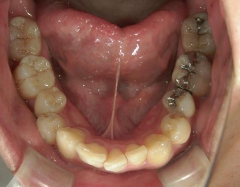

矯正歯科 治療前矯正歯科 治療前

矯正歯科 治療前 上顎の左右4番計2本を抜歯し叢生を改善。